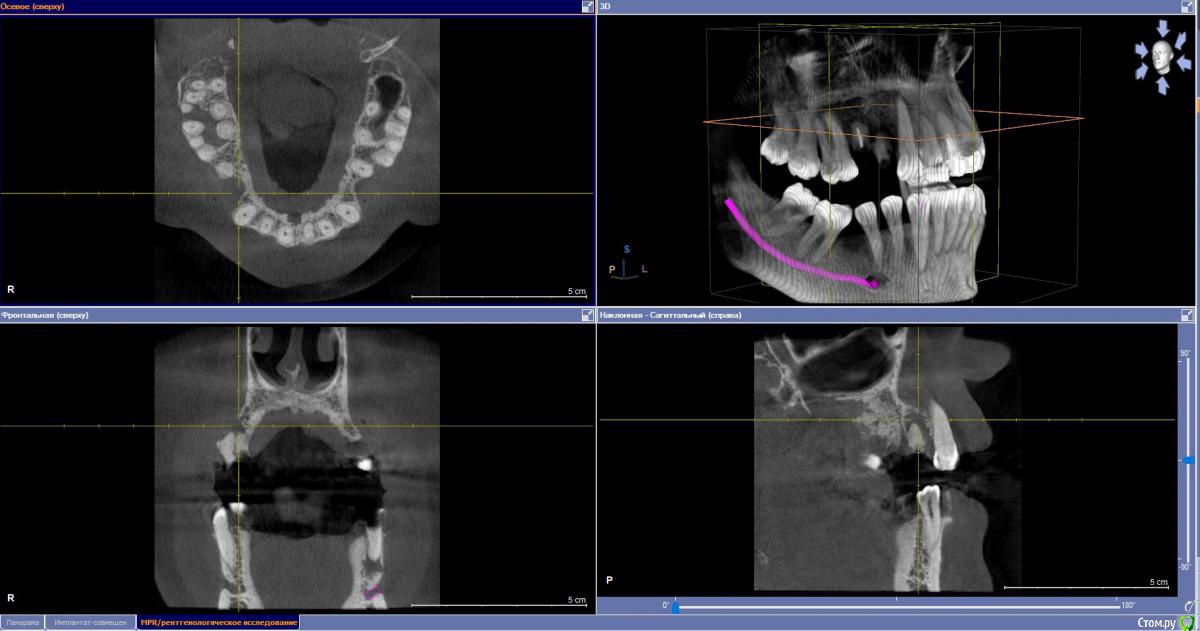

stomalolog Опубликовано 30 ноября, 2018 Поделиться Опубликовано 30 ноября, 2018 Добрый день. Пациенту назначили удаление корней 14,15. Вокруг 14 очаг резорбции, отсутствует вестибулярная стенка, на уровне шеек чуток кости.Собственно вопрос - что после удаления лучше сделать, для образования кости, сохранения десны ? Планируется мостовидный, но в любом случае уйдет десна, если ничего не сделать, не хочется получить яму. И пациент может созреть для имплантации.Какие варианты? A-prf и сверху сразу временные для формирования овоидов и поддержки, или графт-мембрана? Что лучше и может какие еще варианты ?Спасибо. Ссылка на комментарий